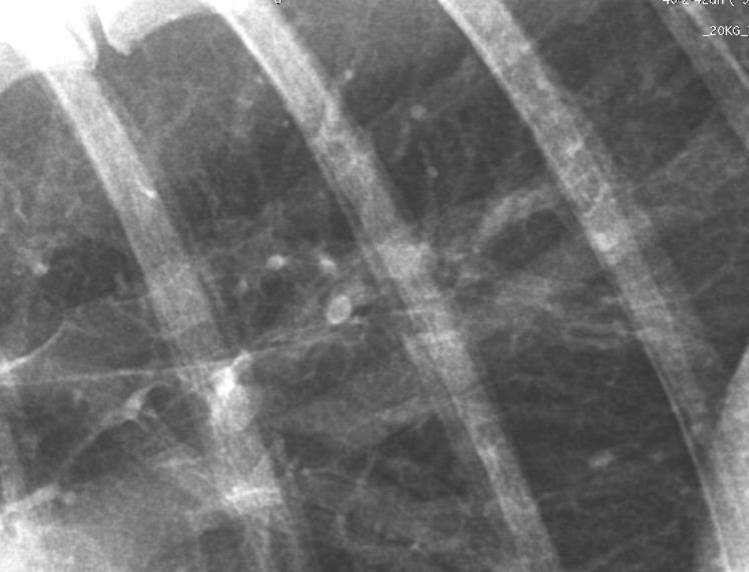

Describe bronchial thickening?

Bronchi can become thickened and will be seen further out towards the periphery, more so than usual – parallel lines called TRAM LINES and doughnuts.